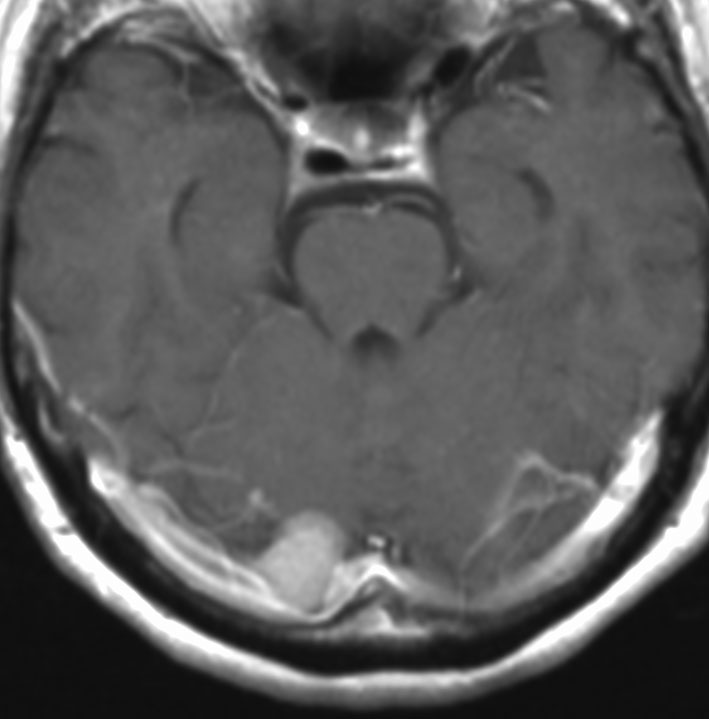

典型的な髄膜腫

この髄膜腫は中程度の大きさのものです。円蓋部髄膜種という最も多い最も手術の簡単なタイプです。麻痺や失語症やてんかんなどの症状はありません。とても美しくて若い女性の髄膜腫でしたが,子供に遺伝はしませんし,癌などと違ってタバコなどこれといった原因がなくて発生するものです。

MRIでの髄膜腫の見え方は撮影の仕方によっていろいろです。左からT1強調画像,T2強調画像,フレア画像といいます。腫瘍の横に小さく白い領域がありますが,これは脳の腫れた部分で脳浮腫といいます。髄膜腫があると周囲に脳浮腫が生じることがあります。

最も見やすいのが,ガドリニウム造影剤を注射して撮影するものです。一般的に髄膜腫は造影剤で白く映し出されます。この腫瘍は左脳側にあります。MRIの軸面という輪切りの写真では左右が逆になりますから注意してください。脳を下から見た図になっています。MRIはいろいろな方向から腫瘍を見ることができますが,右は冠状断という正面から見た図です。よく見ると腫瘍の上と下のはじっこに線状に糸を引いたように造影される部分があります。これをテールサイン(しっぽのサイン)といいます。腫瘍が硬膜に沿って延びている可能性があることを示しています。